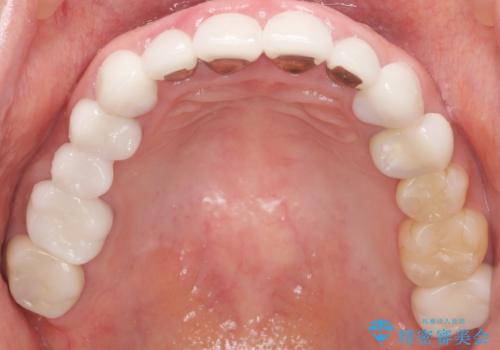

かぶせものと歯ぐきの境目が黒い 40代女性

- 被せ物と歯ぐきの境目が黒いことを気にされ、来院された患者様です。

精査したところ、メタルボンドクラウンの金属部分が露出し黒く見えていました。

患者様のご希望により、金属を使わないオールセラミックのブリッジによる補綴治療を行いました。

金属の土台も除去し、ファイバーコア(金属を使わない強度のあるしなやかな土台)へやりかえました。

自然な仕上がりと咬み心地に喜んで頂けました。

クラウンの種類:オールセラミッククラウン スタンダード